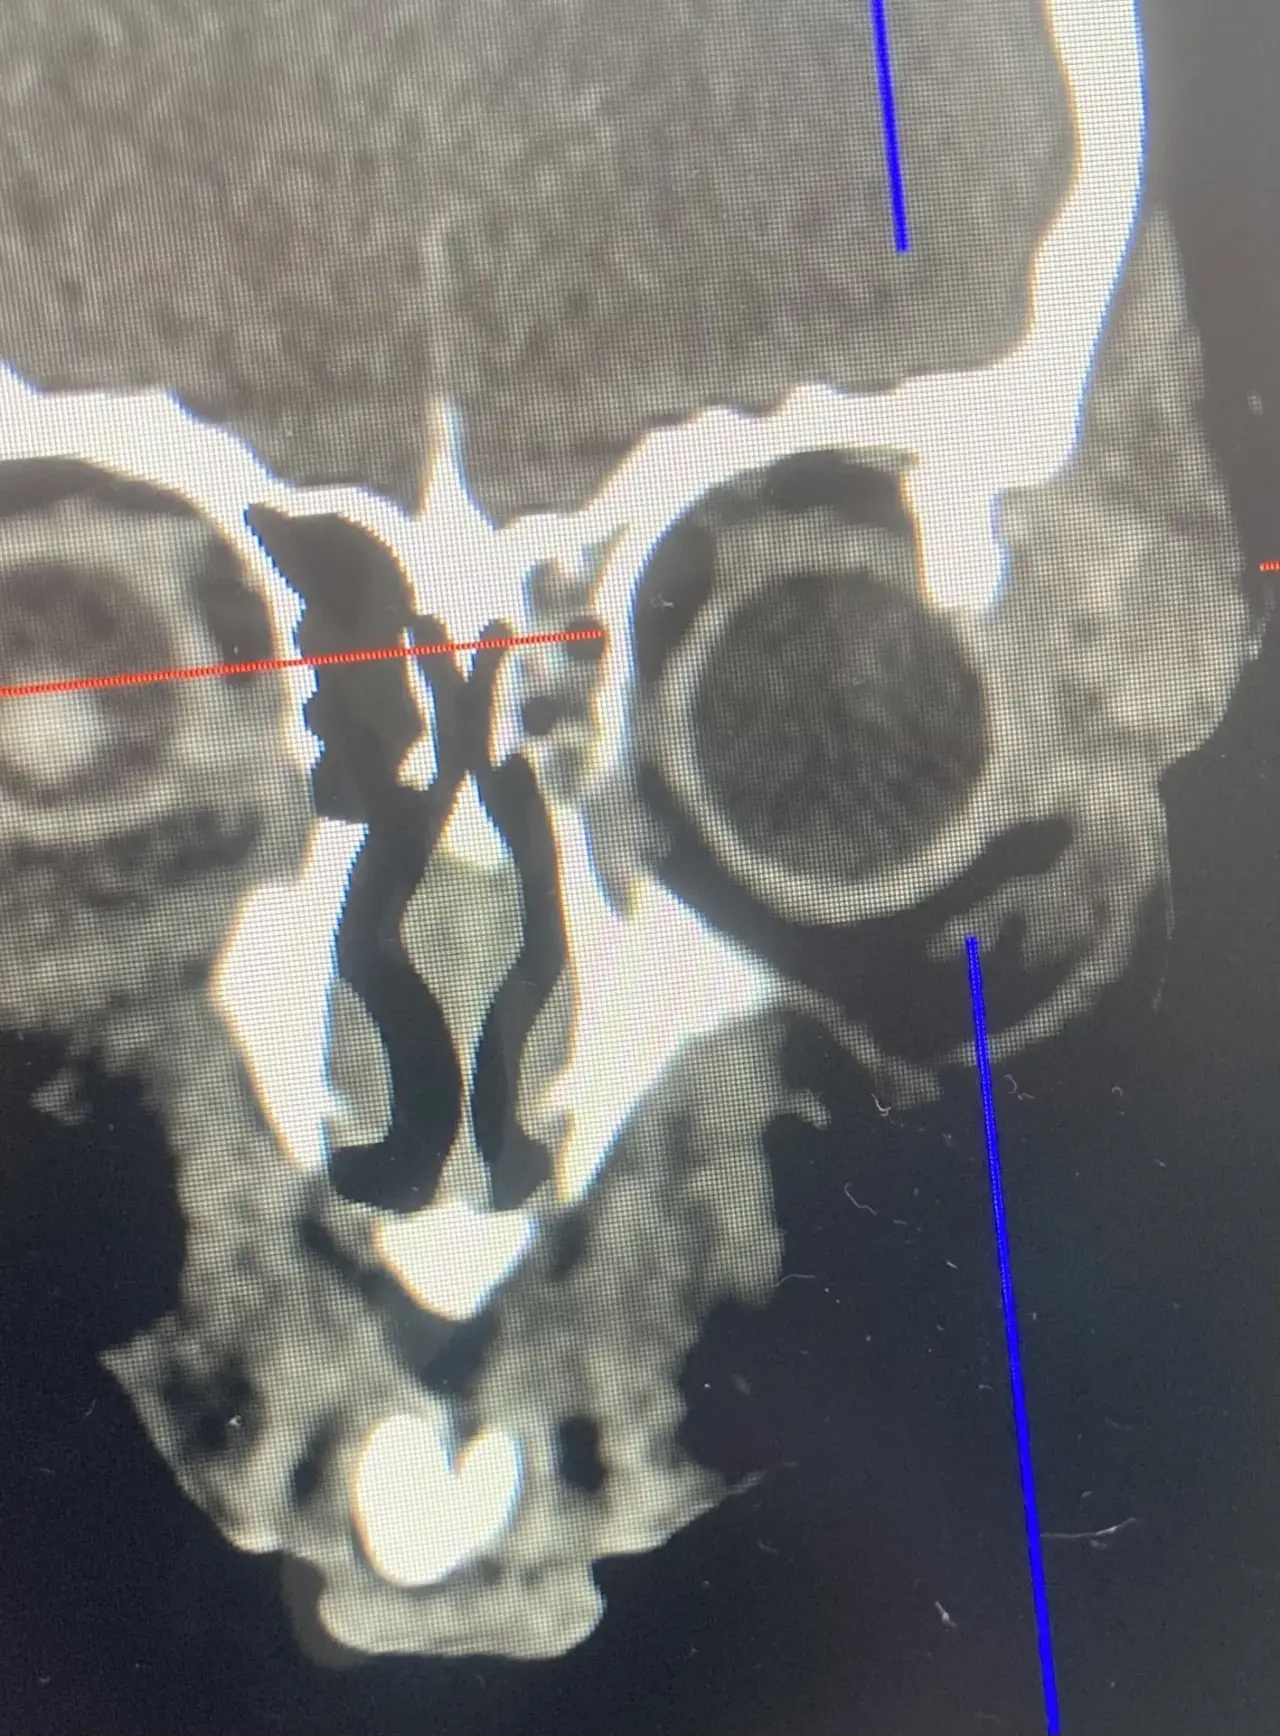

Врачи ОДКБ успешно провели операцию 8-летней девочки, на которую упала ледяная глыба. Несчастный случай произошел в Кольчугино на улице Кима 20 марта. Ребенка экстренно госпитализировали с черепно-мозговой травмой и сложным переломом в области верхнего края левой глазницы.

Один из осколков кости сместился внутрь и повредил глазное яблоко. Ребёнка доставили в Областную детскую клиническую больницу, в хирургическое отделение №1. Как рассказывают врачи, операция потребовала от врачей максимальной точности и слаженности действий: необходимо было не только восстановить правильное положение костных фрагментов, но и устранить повреждение глаза.